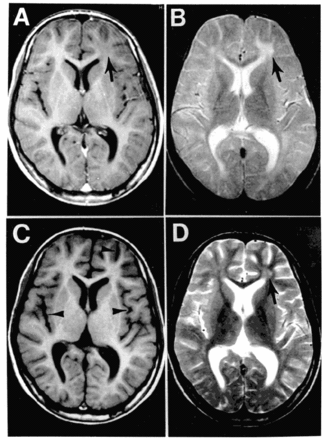

![]() Магни́тно-резона́нсная томогра́фия (МРТ) больного ПСПЭ | |